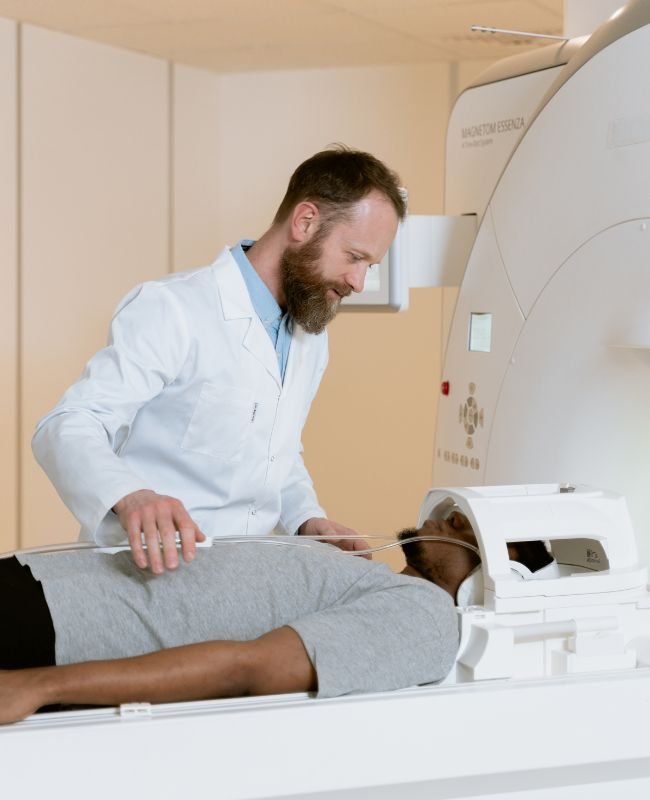

Servicios Radiológicos en Madrid que combinan tecnología avanzada y experiencia profesional para ofrecer diagnósticos rápidos y confiables. En nuestro centro, realizamos una amplia variedad de pruebas, desde radiografías hasta resonancias magnéticas, siempre adaptándonos a las necesidades específicas de cada paciente.

Además, garantizamos una atención cercana y personalizada durante todo el proceso, facilitando que te sientas cómodo y seguro. Por otro lado, nuestro equipo médico trabaja con rigor para entregar resultados precisos que permitan un diagnóstico oportuno y eficaz.

En nuestro Centro Radiológico en Madrid, ofrecemos soluciones completas para todas tus necesidades de diagnóstico por imagen. Gracias a la combinación de tecnología avanzada y un equipo médico especializado, garantizamos estudios fiables que facilitan un diagnóstico temprano y un tratamiento efectivo.

Asimismo, comprendemos la importancia de un trato cercano y personalizado, por lo que cada servicio está diseñado para brindarte comodidad y confianza durante todo el proceso. Por lo tanto, nuestras soluciones están orientadas a cuidar tu salud con la máxima precisión y calidad.